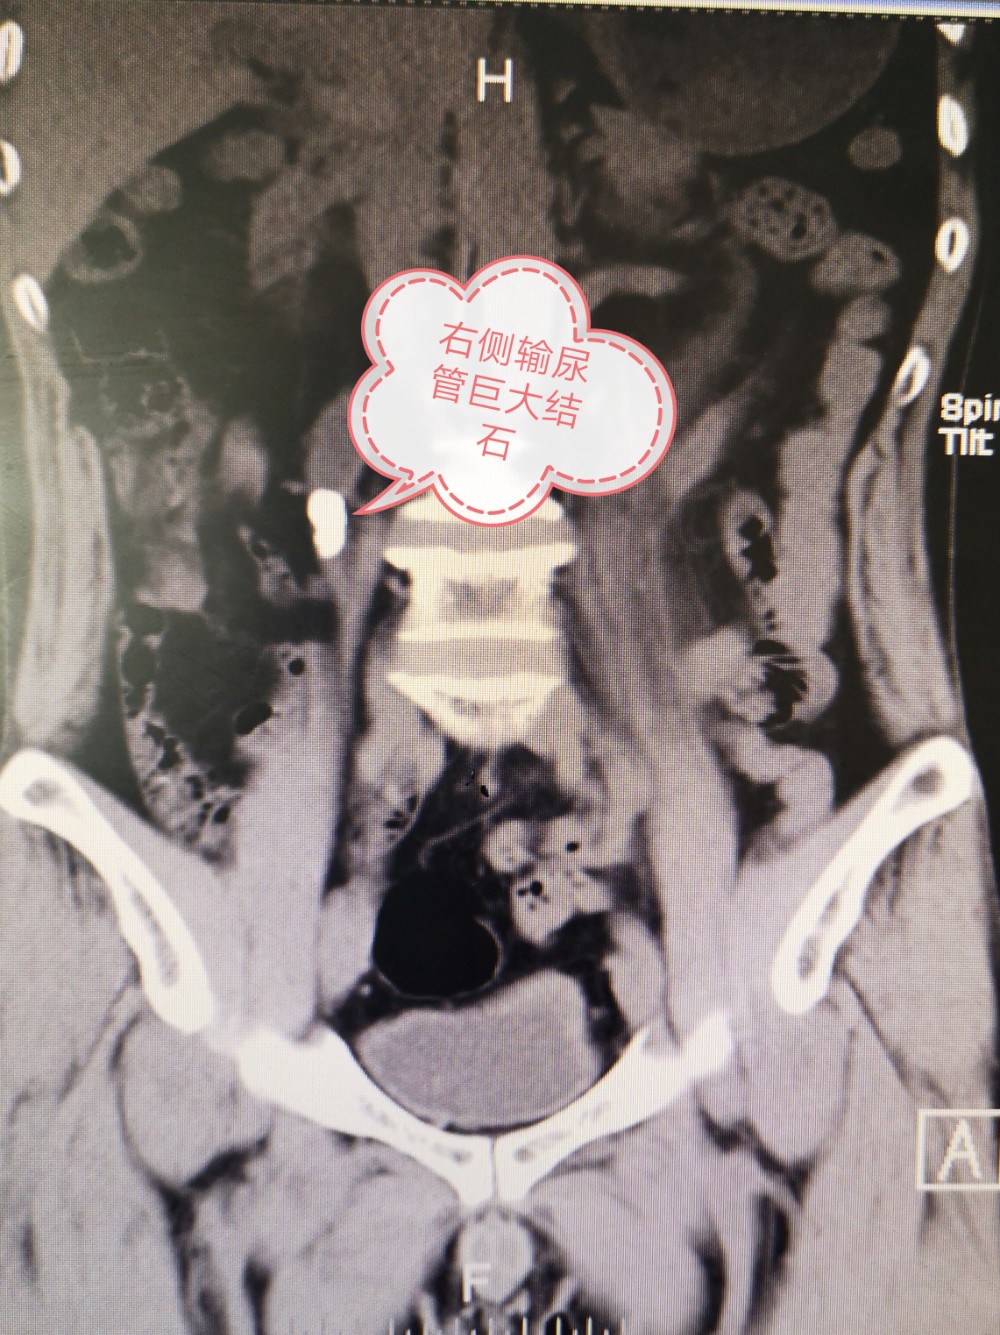

郑九院图片新闻(2021.5总60):泌尿外科1小时帮输尿管结石出现肾绞痛患者解围

近日,郑州市第九人民医院泌尿外科完成一台腹腔镜输尿管切开取石术。患者因左侧输尿管结石出现肾绞痛急诊入院,检查发现右侧输尿管上段结石,结石长期梗阻导致右肾重度积水,结石周围大量息肉形成,手术一个小时顺利完成,完整取出结石,患者右侧无任何不适症状。

专家提醒:输尿管结石典型表现为肾绞痛,但也有少部分没有明显症状,这种情况危害更大,往往体检发现时肾脏已无功能,需要特别重视。